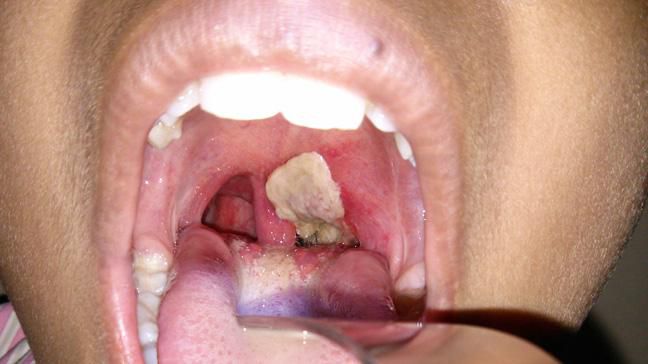

Speaking on the rising cases of the disease at a press conference on Monday, the Director-General of the Nigeria Centre for Disease Control and Prevention (NCDC) Dr. Ifedayo Adetifa said that out of the 8,406 cases in Nigeria, 73.7 % of the victims were between one year and 14 years.

Adetifa said, “As of today (yesterday), there have been 13,204 reported suspected cases out of which 8,406 were confirmed cases from 114 local government areas in 19 states and the FCT.

“Of the 8,406 confirmed cases, 6,202 (73.7 %) were aged one to 14 years. Infants: less than 1%; one to four years: 14.40%; five to nine years: 32.2%; 10 to 14 years: 27.1%; adults above 20 years: 15%

“Our records have shown that most of the confirmed cases of diphtheria in the country were unvaccinated against diphtheria.